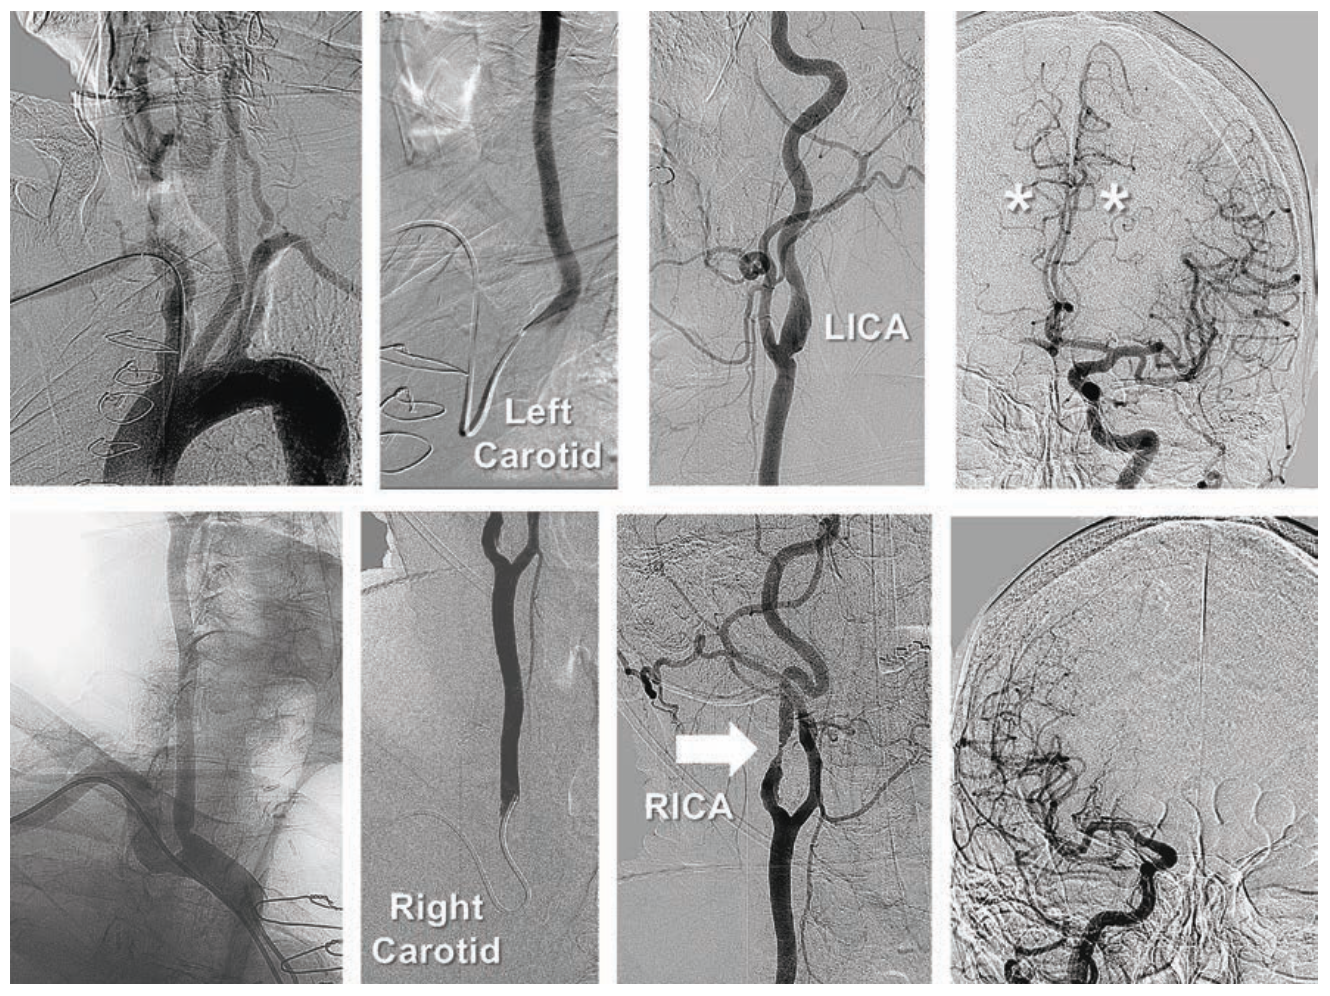

Case #5

A 75-year-old female (5 feet 10 inches, 178 cm in height) had undergone remote bilateral “kissing” iliac stents extended into the aorta using bilateral femoral artery access, complicated by access site hemorrhage requiring blood transfusions and prolonged hospital stay. She presented with recurrent and debilitating left leg claudication. Resting ABI in the right leg was 0.94, unchanged with exercise. In the left leg, her ABI fell from 0.64 at rest to 0.48 with exercise. She refused to consider repeat femoral artery access for angiography or intervention. Diagnostic angiography performed using 5 Fr left TRA demonstrated patent common iliac artery stents, with a new heavily calcified and eccentric left external iliac artery stenosis (Figure 5). A 150 cm Trailblazer catheter was used to direct a 300 cm Wholey guidewire through the left iliac artery stent, across the lesion and into the SFA. This catheter was exchanged for a 110 cm Flexor Shuttle sheath advanced beyond the proximal edge of left common iliac artery stent. Over a 300 cm .014-inch coronary guidewire, the external iliac disease was treated with a Viatrac 14 Plus RX 5 mm x 15 mm balloon, with severe lesion recoil. Two overlapping Herculink Elite RX 7 mm x 18 mm BE stents were deployed, with excellent angiographic results. The patient was discharged 3 hours later following use of a TR Band.

Tips and Tricks for 5 Fr Stenting Through “Kissing” Iliac Stents

Left TRA allows additional purchase of up to 8 cm further into the lower extremity circulation than right TRA. Left TRA is preferred for reaching distal external iliac artery disease in taller patients, and in those with very tortuous aortoiliac anatomy, as both circumstances increase the intravascular distance needing to be traversed. In this patient, heavily calcified eccentric external iliac artery disease necessitated BE instead of SE stent technology, with stent delivery facilitated by first advancing the Flexor Shuttle sheath with its introducer through the left common iliac stent. Stored images obtained in higher magnification during PTA balloon inflation allowed appropriate sizing of the Herculink Elite RX BE stents to 7 mm.